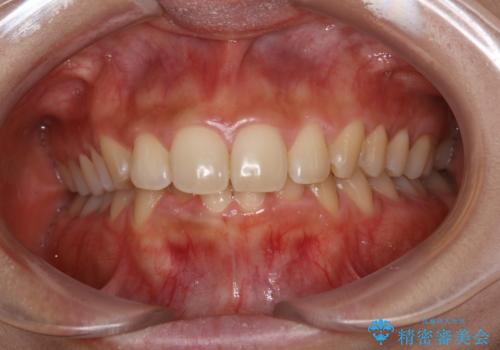

- 1か月後に結婚式があるため、歯を白くしたいとのことでした。

オフィスホワイトニング(TION Whitening・処置前クリーニング込み)コースを行いました。

事前に痛み止めを服用して行った為、施術中の痛みを感じることなく受けていただくことができました。

ご希望の自然な白さに、トーンアップしたとのことで満足していただけました。